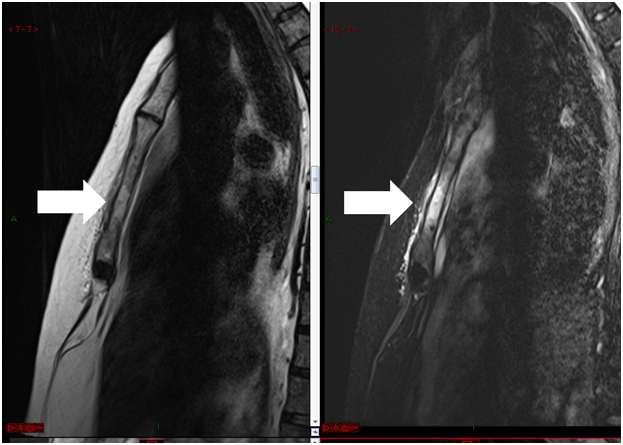

Figure 4 Magnetic resonance shows a left humeral lesion of neoplastic appearance.

The patient consulted with a cardiology team where an electrocardiogram and an exercise test were performed, being reported normal. He was then referred to the orthopedics service due to shoulder pain persistence. A shoulder x-ray showed a tumor in the left thorax measuring 78.99mm in diameter (Figure 1). In follow up studies, a left humeral lesion of neoplastic appearance was revealed. In the magnetic resonance an intramedullary lesion is reported in the sternum, incidentally, a solid mass is observed in the left lung, it also shows tendinitis of the rotator cuff and subacromial impingement (Figures 2-4). Therefore, it is decided to perform a Computed Tomography scan which reported atelectasis mainly in the left upper lobe and a tumor measuring 65mm (Figure 5). The Positron Emission Tomography - Computed Tomography scan result was an increase of the metabolism by neoplastic activity, lymphadenopathy and bone lesions, hepatosplenomegaly and non- specific alterations in the colon (Figure 6).